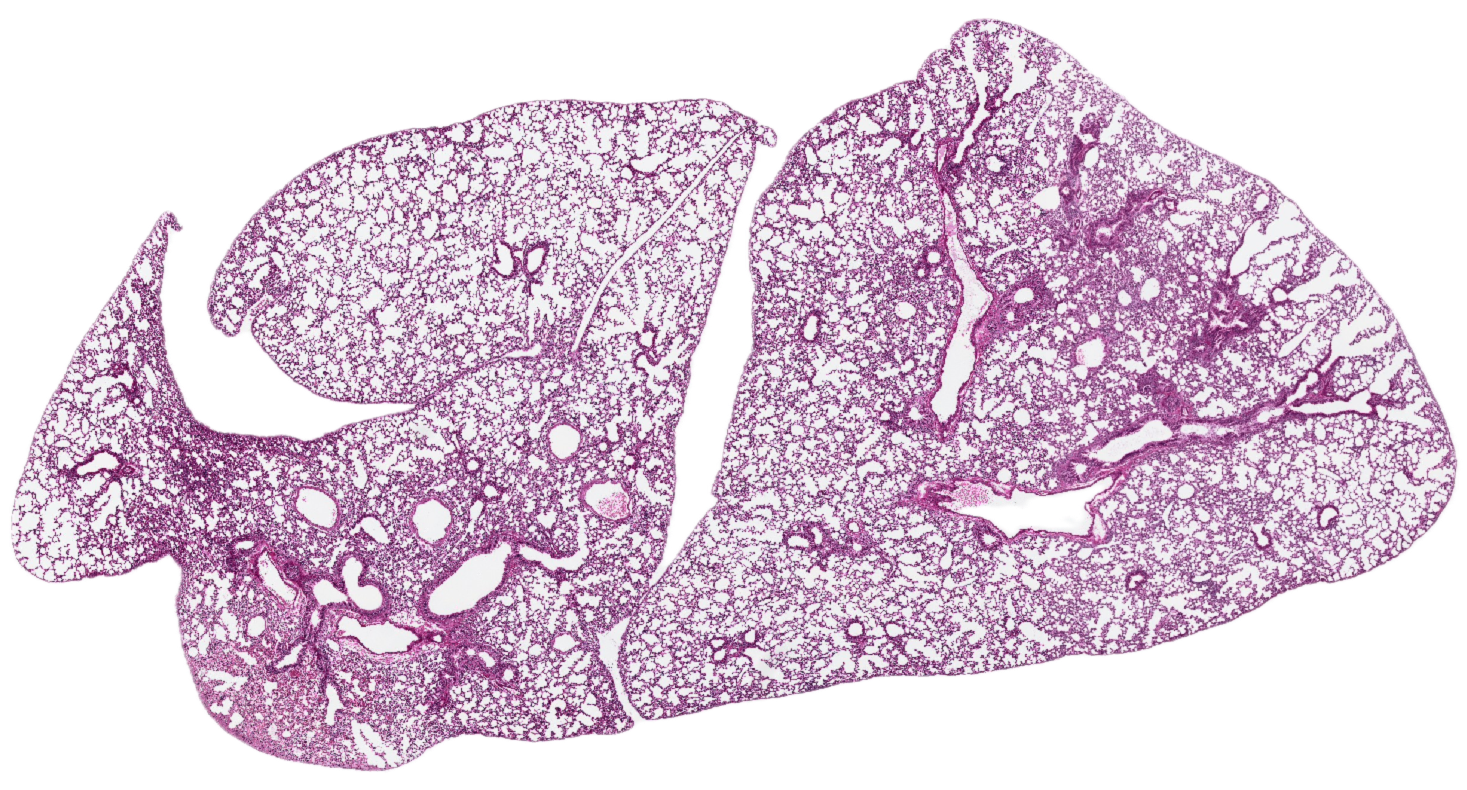

Los escáneres o digitalizadores de láminas son microscopios automatizados capaces de capturar imágenes digitales idealmente en alta resolución a partir de láminas histológicas físicas. Existen distintos modelos según el volumen y la aplicación clínica, pero para diagnóstico deben cumplir estándares estrictos de calidad y precisión.

Digitalizamos tus láminas y entregamos archivos listos para diagnóstico, revisión o docencia, con imágenes de alta resolución que cumplen estándares internacionales y que pueden ser fácilmente integradas por sistemas LIS.